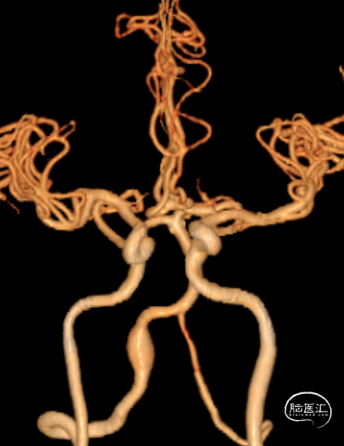

CTA:

右侧椎动脉(优势侧)V4段梭形动脉瘤,

左侧椎动脉纤细,后交通动脉未显影。

影像科提供的重建图像就像美颜照片,虽然好看,但丢失了诸多细节。

我们使用影像工作站重建的图像能够看到更多细节:

动脉瘤处有明显的凹陷,考虑为动脉夹层的内膜瓣;动脉瘤累及小脑后下动脉(PICA)的开口。

3D造影:动脉瘤处有明显的凹陷,符合夹层内膜瓣表现;PICA从动脉瘤远端发出,动脉瘤大小约6.5×12.8mm,受累椎动脉直径约4.3mm,覆盖远近端达正常血管约需30mm支架长度。